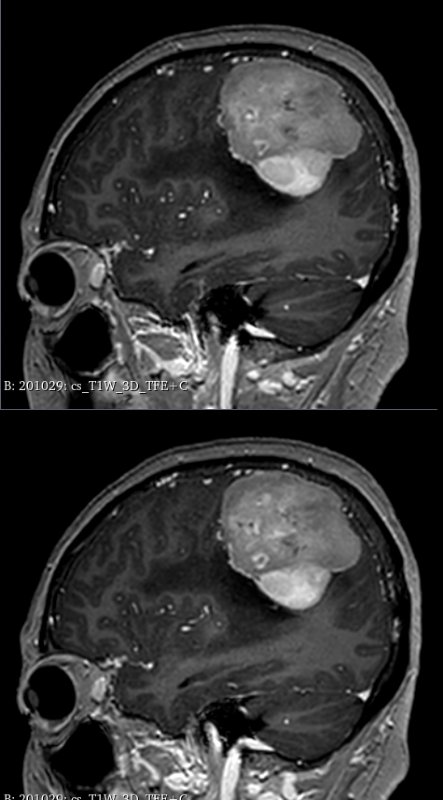

据悉,该患者因“间断头痛4年、加重伴头晕4个月”就诊。头颅MRI检查显示,其右侧顶部巨大占位紧邻中央沟功能区及上矢状窦等重要血管。

术前精准建模:运用3D Slicer软件整合多模态影像数据重建三维模型,清晰呈现肿瘤与周边功能区、血管的空间关系,为手术规划提供精准数字化依据。